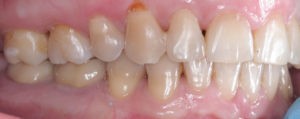

Пациентка довольна профилем и красивой улыбкой.